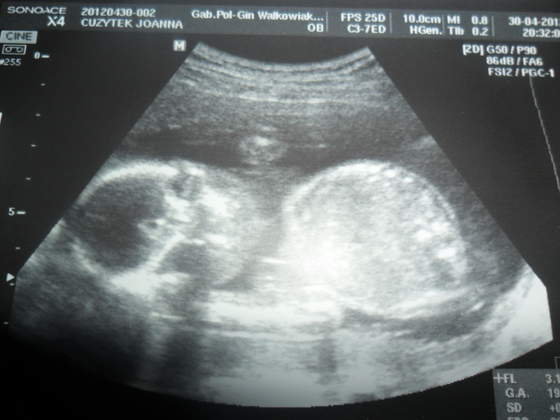

Niunia zdrowa wszystko ma na swoim miejscu a pierwsze co pokazala to cipuche bedzie Coreczka, czyli Mama sie nie mylila hehe spala sobie grzecznie na jednej raczce pod glowka a kiedy PAni gin chciala ja obudzic to zakryla buziunie raczkami i stwierdzilismy ze nie bedziemy jej meczyc

wazne ze wszystko zdrowiutkie i na swoim miejscu wazy juz 300 gramow jest przecietniaczkiem jak ujela gin, aha powiedziala ze poki co mam lozysko na tylnej scianie ale moze sie to zmienic, to zle ze jest na tylniej???

A to nasza Corcia poki co Lilianna

a tu balerina pokazuje co ma miedzy nóżkami